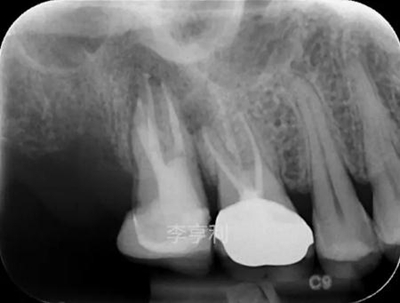

【輔助檢查】: CBCT見(jiàn)17冠部大面積充填物阻射影,接近髓室底,根管內(nèi)充填物錐度尚可,距根尖均為2mm以?xún)?nèi),根尖周大范圍阻射影主要在頰根區(qū)域,波及16的DB根尖區(qū)域,頰腭側(cè)骨板完整